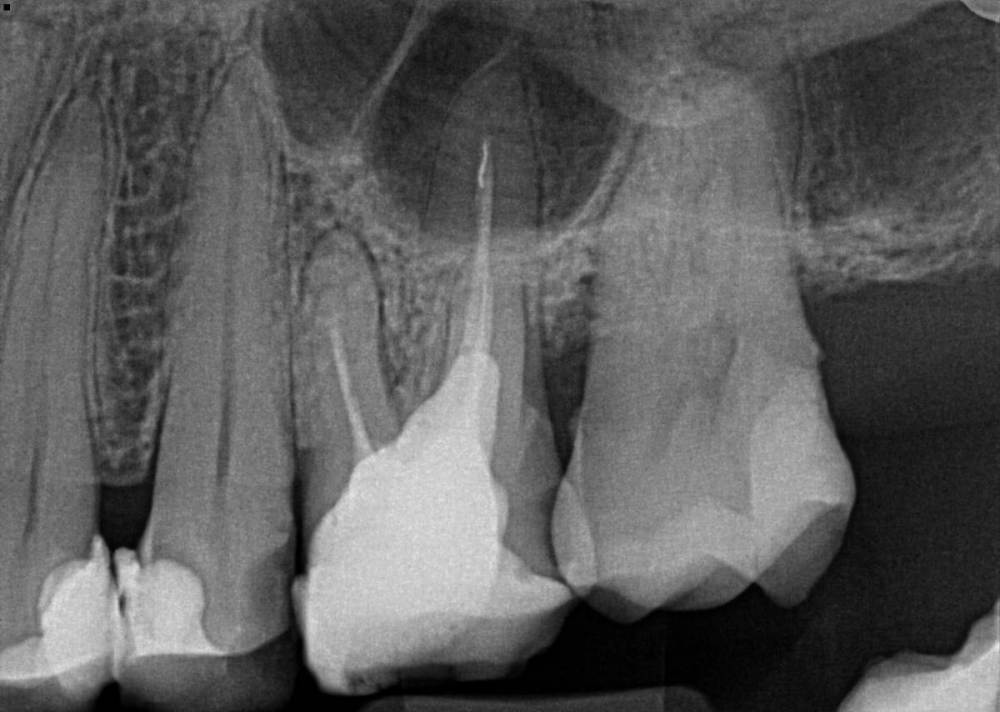

elenaterra Опубликовано 22 декабря, 2021 Поделиться Опубликовано 22 декабря, 2021 (изменено) Проживаю в США в Лос Анджелесе, перед отъездом полечила все зубы, так как знала что здесь очень дорого, да и доверяю только своему стоматологу, к которой хожу лет 20. Так вот где то год назад на нижнем моляре (крупный самый жевательный) снизу слева выпала пломба и там была дыра. Так как денег не было и была депрессия, апатия, зуб не болел и не знала куда идти, я прокрастинировала. Начал он болеть месяц назад, потом прошел, знаю что надо было сразу бежать лечить, но уже есть как есть. В общем он ныл только когда в дырке еда оставалась, я зубочисткой чистила и вроде ок опять. Позавчера поела еду, которую обычно не ем (орехи, каша какая то смесь всего). Ну и начал интенсивно болеть, боль терпимая, но уже на грани. Помогает раствор соль плюс сода. Оформила кредитку местную на лечение, но она все равно не покроет и половину лечения. В одну клинику сегодня позвонила, вроде бы хорошие отзывы, 125 баксов прием первичный посмотреть, они перенаправили к специалисту по Рут каналам из другой клиники. Я позвонила, стоимость Рут канала 1700 это без пломбы, пломбу потом в другой клинике делать. Прием посмотреть 150 долларов. Рассрочки нет никакой у них. Позвонила в другую тоже очень хорошую по отзывам, оказалась можно приехать прямо сейчас. Они сделали три снимка ( у меня ещё две пломбы выпали, но не болят пока что). По итогу несколько зубов удалять, импланты ставить, другую половину коронки и всякий кариес по мелочи. Воспаление мелкое она сказала, вроде как организм мой борется, она так сказала. Этот зуб который болит сказала удалять, я просила Рут канал, сказала очень маленькие шансы на успех и выйдет в тысячи долларов и кучу времени, зато можно вырвать за 500 и поставить имплант и будет как новый (так и сказала). Клиника одна из лучших, отзывы почти все хорошие. Также нашла кусок инструмента который якобы мой стоматолог оставила в другом зубе. Я спросила это точно кусок инструмента (так как своей доверяю и она инструменты не оставляет и после всегда делает снимок), она надо все раскрыть и посмотреть, скорее всего да, вроде как не уверена. Мой вопрос можно ли сохранить зуб или хотя бы попытаться или врач права и только вырывать? Снимок прикрепляю. Ps если можно сохранить, думаю лететь домой, так как здесь у меня вообще доверия не вызвало ничего, даже бахил у них нет, страшно было Изменено 22 декабря, 2021 пользователем elenaterra Ссылка на комментарий

elenaterra Опубликовано 22 декабря, 2021 Автор Поделиться Опубликовано 22 декабря, 2021 Спасибо вам большое! Я сейчас пытаюсь найти русскоговорящего стоматолога, здесь я так поняла есть еврейские стоматологи либо армянские, у еврейского я была, но к нему сразу не попасть, а только через врача, который меня смотрела и нужно было несколько зубов удалять. Тот где инструмент и ещё один снимок где дыра и рядом с инструментом либо удалять либо Рут канал делать В общем только что я запомнила три зуба удалять, по моему ещё какие то она говорила тоже надо удалить Ссылка на комментарий